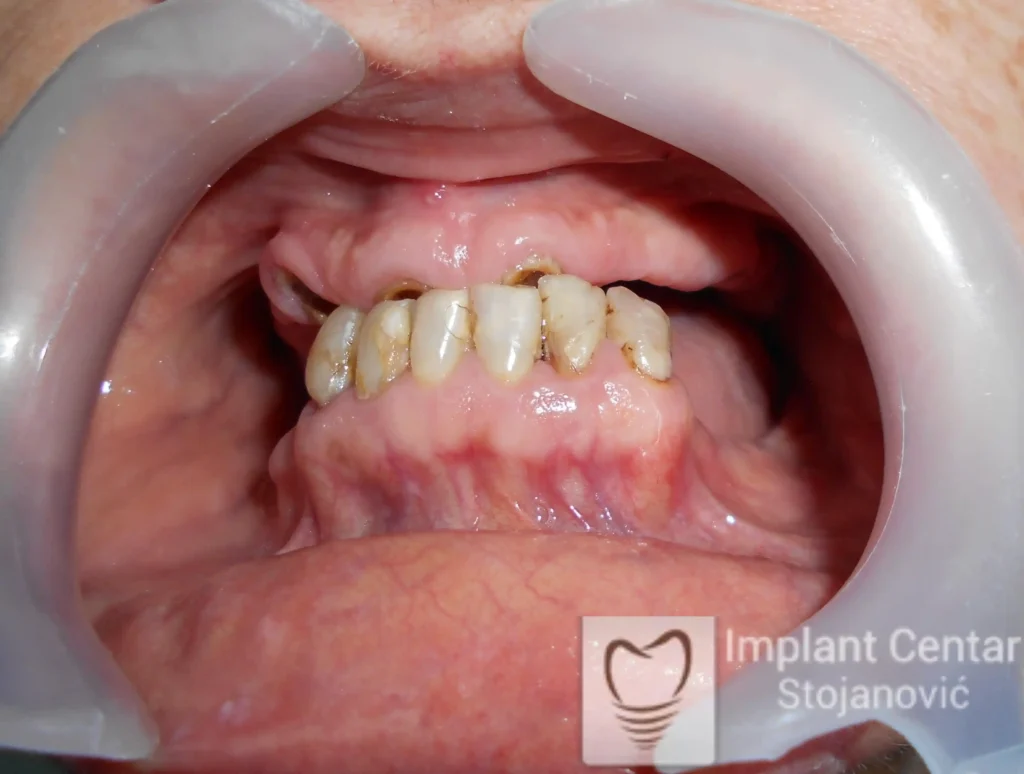

Pacijent sa rascepom usne, nepca i alveolarnog grebena uspešno je rehabilitovan fiksnim protetskim radom na implantatima. Pre dolaska u našu ordinaciju, pacijent je u gornjoj vilici nosio totalnu protezu preko preostalih zuba, dok je u donjoj vilici bio zbrinut parcijalnom mobilnom protezom. Tokom višegodišnje potrage za adekvatnim rešenjem, pacijent nije uspeo da pronađe zadovoljavajuću terapijsku opciju ni u zemlji ni u inostranstvu.

Nakon detaljnog kliničkog pregleda i analize radioloških snimaka, izrađen je sveobuhvatan plan terapije sa ciljem uklanjanja mobilnih proteza i postizanja maksimalne funkcionalne i estetske rehabilitacije. Zbog loše biološke vrednosti preostalih zuba, doneta je odluka o njihovom vađenju i ugradnji dentalnih implantata.

Poseban terapijski izazov predstavljalo je premošćavanje defekta nastalog usled rascepa, kao i ograničena količina raspoložive kosti u gornjoj vilici. Primenom većeg broja implantata i odgovarajućih procedura nadoknade kosti, postignuta je stabilna osnova za fiksni protetski rad.

Tokom perioda oseointegracije, pacijent je bio zbrinut fiksnim privremenim krunicama, čime je već pet dana nakon intervencije obezbeđena potpuna funkcionalna i estetska rehabilitacija. Nakon završetka perioda integracije implantata, izrađeni su definitivni cirkonijum-keramički mostovi na implantatima.